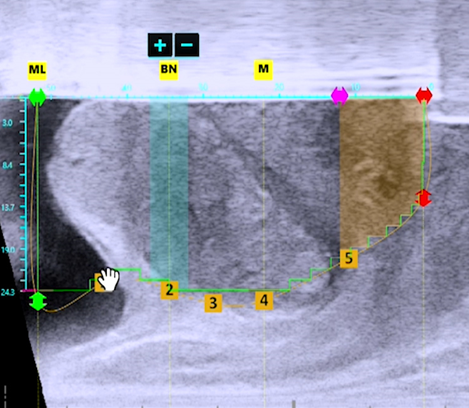

초음파와 내시경을 동시에 실시간으로 확인하며 절제할 조직과 보존할 조직을 정확히 설계

아쿠아블레이션은 크기에 관계없이, 비대조직의 모양에 관계없이 수술적 치료가 가능합니다. 중엽비대가 심하거나 방광경부거상이 심한 경우 일부 수술 방식으로는 효과가 제한적이어서 적용이 어려웠다면, 아쿠아블레이션은 모든 양상의 전립선 비대증에 적용이 가능합니다.